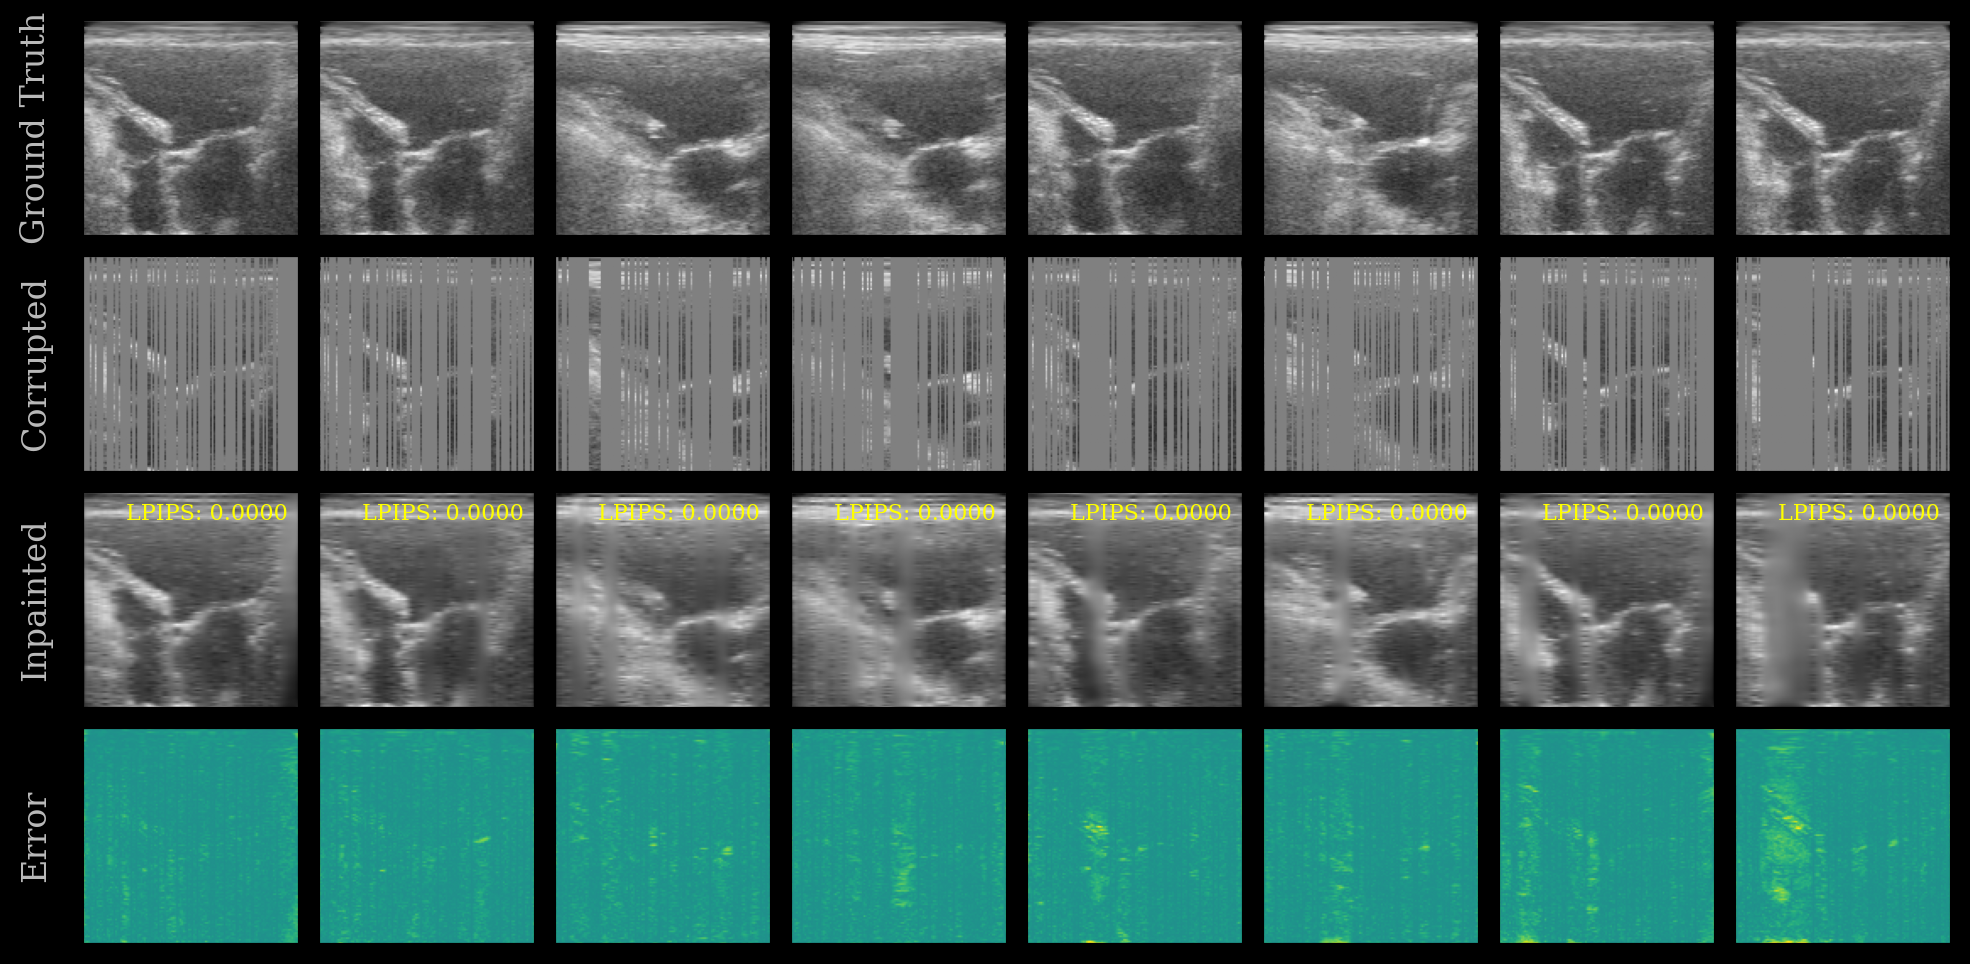

We plot the ground truth, corrupted, inpainted, and error images. The LPIPS score is shown on each inpainted image. Note that this model was trained on the EchoNet-Dynamic dataset, whereas we are testing now on the CAMUS dataset.

[10]:

UNet Inpainting Results

You can try other UNet presets or experiment with different masking strategies to explore the capabilities of zea.Models!